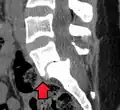

![]() | |

| X-ray of the lateral lumbar spine with a grade III anterolisthesis at the L5-S1 level | |

(A) CT sagittal view of a low grade slip.

(B) Lateral radiograph pre-operative intervention.

(C) Surgically treated with L5–S1 decompression, instrumented fusion and placement of an interbody graft between L5 and S1.